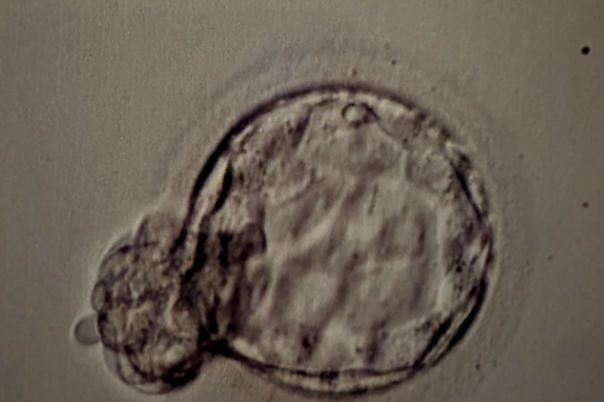

胚胎发育的马拉松,一文了解养囊胚到底需要几天

实验室里的胚胎培养箱就像个微型子宫,静静见证着生命最初的奇迹。近三年生殖医学中心数据显示,约65%的优质胚胎能在5-6天完成囊胚转化,这个被称为「黄金窗口期」的阶段,决定着后续移植成功率的关键。不过您可别小看这几天,胚胎在这期间经历的可是真正的「优胜劣汰」——据统计,仅有40%-50%的胚胎能坚持到最终形态。一、实验室里的时间魔法受精卵第3天还只是个8细胞「小团子」,到第5天就能长成上百细胞的「小

12个胚胎能养出多少囊胚?这些实验室不会说的真相

走进生殖中心的人,大多听过这句灵魂拷问:取卵十几个,最后能用的囊胚有几个?今天我们就用实验室数据说话,聊聊这个关乎试管成败的「数学题」。一、胚胎到囊胚的惊险跳跃培养箱里的胚胎就像参加生存游戏的选手。取卵后第三天,正常发育的胚胎应该有8细胞,这时候实验室会淘汰掉发育迟缓或碎片过多的「差生」。有经验的胚胎师打了个比方:「我们见过太多戏剧性转折,第3天还活蹦乱跳的胚胎,到第5天突然停止发育。就像跑马拉松